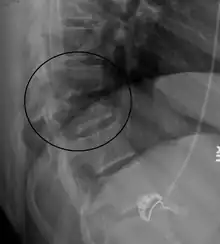

A Chance fracture of T10 and fracture of T9 due to a lapbelt during an MVC.

On plain X-ray a Chance fracture may be suspected if two spinous processes are excessively far apart.[8]